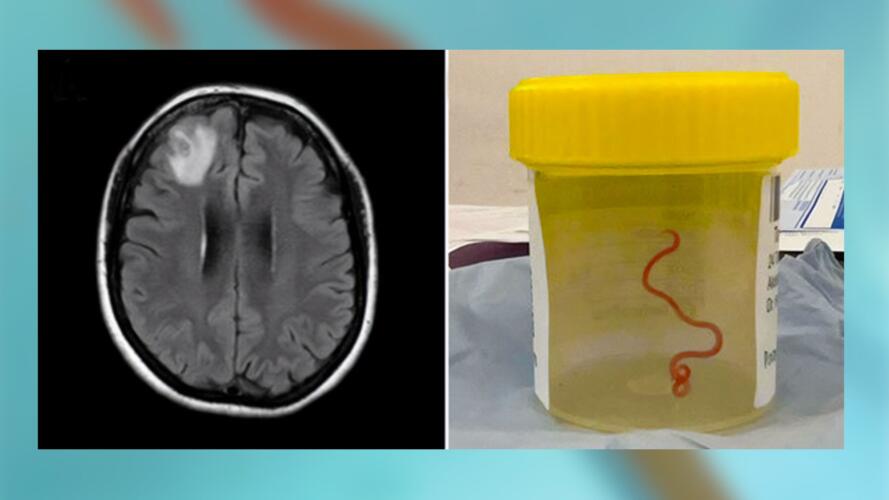

دخلت المريضة لأول مرة إلى المستشفى المحلي في أواخر شهر يناير/ كانون الثاني 2021 بعد تعرضها لإسهال وآلام في البطن لمدة 3 أسابيع، أعقبها سعال جاف وتعرق ليلي وحمى. بحلول شهر يونيو/ تموز 2022، بدأت تعاني أعراض النسيان والاكتئاب، وبسبب هذه الأعراض الجديدة، أُحيلت إلى مستشفى كانبيرا (Canberra Hospital) لتلقي العناية الطبية. في أثناء وجودها في المستشفى، خضعت لعملية جراحية في الدماغ عندما كشف التصوير بالرنين المغناطيسي عن بعض التغيرات غير الطبيعية في الدماغ.

وخلال أخذ عينة من الأنسجة، استخدمت جرّاحة الأعصاب، هاري بريا باندي (Hari Priya Bandi) ملقطاً لسحب الدودة الطفيلية من دماغ السيدة. وفقاً لصحيفة الغارديان، اتصلت باندي على الفور بطبيب الأمراض المعدية في مستشفى كانبيرا، سانجيا سينانايكي (Sanjaya Senanayake)، وقالت له: "يا إلهي، لن تصدق ما وجدته للتو في دماغ هذه السيدة؛ إنها دودة على قيد الحياة وتتحرك بنشاط"!